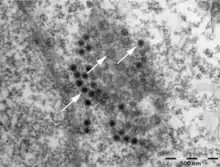

For diagnosis, the erythrocytes can be isolated by injecting them into a tissue culture and checking to see if they are infected. Also, the antigen for Colorado tick fever virus can be identified using the immunofluorescence microscopy. In this method, the antigens on the surface of the erythrocytes are marked with fluorescence and examined under a fluorescence microscope.[5]